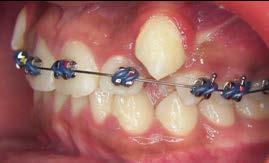

Tratamiento de caninos retenidos superiores en paciente en crecimiento con clase II división 2. Reporte de caso clínico

Los caninos retenidos constituyen una alteración eruptiva frecuente, con mayor prevalencia en la arcada superior. Su etiología es multifactorial y puede interferir con el trayecto normal de erupción, comprometiendo la oclusión y la estética.

Objetivo: Corregir una maloclusión Clase II división 2 mediante tratamiento ortodóntico en un paciente en crecimiento con ambos caninos superiores retenidos. Metodología: Se presenta el caso de un paciente masculino de 12 años, en dentición permanente, con perfil convexo, patrón dolicofacial y Clase II esquelética. Se realizó tratamiento ortodóntico sin extracciones. Para la tracción y alineación de los caninos retenidos se emplearon resortes abiertos (open coil springs) para la creación de espacio. Resultados: